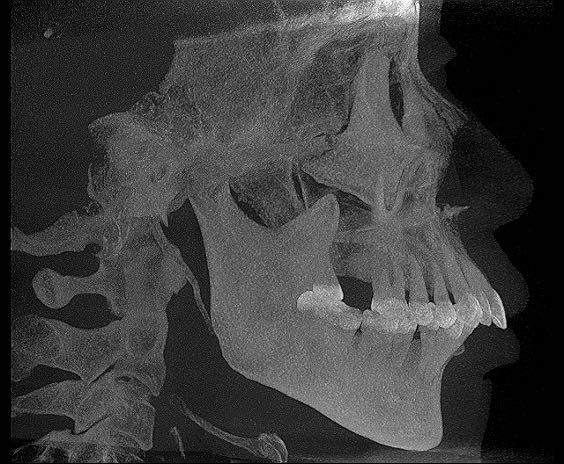

【头颅侧位片】

头颅侧位片